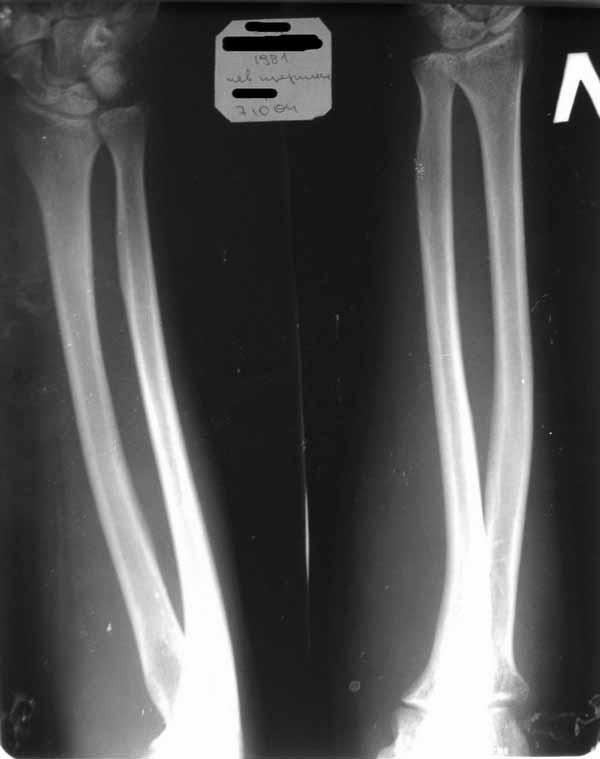

Уважаемые коллеги!Требуется ваша помощь. На консультацию обратился пациент 30 лет с жалобами на ограничение активных движений в левом плечевом суставе.

Пассивные – в полном объеме. Со слов – имела место некая родовая травма. К тому же отмечается незначительный дефицит иннервации n.radialis (снижение «силы» разгибателей-сгибателей в кистевом суставе и отведения 1 пальца; неврологи никакого специфичного лечения не назначают). Также имеется контрактура локтевого сустава: сгибание в полном объеме, разгибание 150 градусов, супинация в пределах 7 градусов. Функция конечности в принципе устраивает. Скелетных травм в анамнезе нет. Вопрос: есть ли смысл заниматься какими-либо реконструкциям на плечевом суставе и как можно улучшить функцию скомпрометированных суставов? Заранее всем благодарен